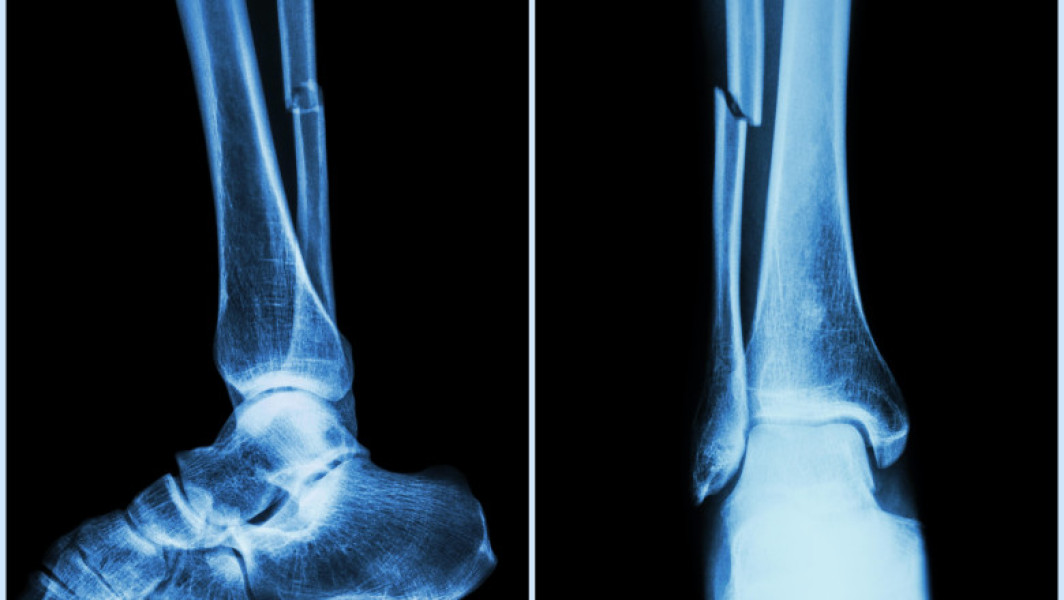

O echipă de studii din provincia Zhejiang, China, cu doctorul Lin Xianfeng în rol de conducere, a elaborat un adeziv osos medical denumit „Bone-02”, capabil să fixeze rapid părţile fracturate în doar câteva minute. Această soluție ar putea să rezolve problema unor metode invazive tradiționale cum ar fi implanturile metalice.

Noul adeziv a fost testat deja cu succes pe peste 150 de pacienţi, iar forţa sa de lipire este de peste 180 de kilograme. Această tehnologie ar putea reduce riscul de infecţii postoperatorii şi alte complicaţii. Specialiştii au reuşit să realizeze această legătură printr-o incizie minimă.